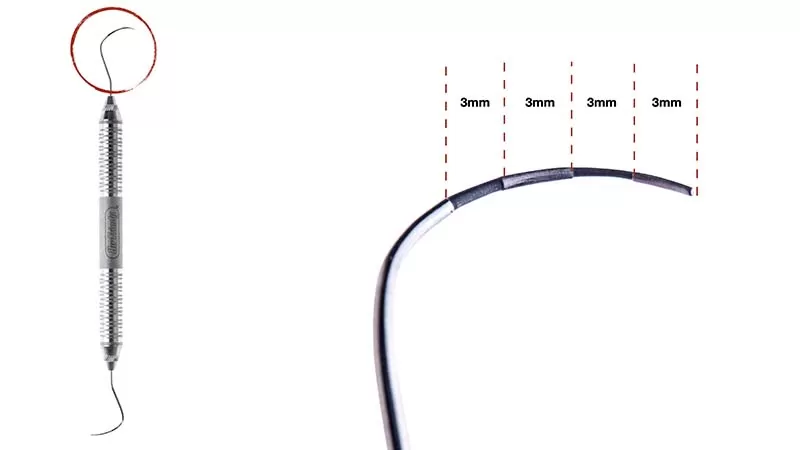

Le sondage parodontal est le gold standard clinique :

- Sonde parodontale graduée classique → pertes d’attache péri-dentaires

- Sonde de Nabers (courbe, millimétrée) → composante horizontale des lésions interradiculaires

- La composante verticale est estimée sur le cliché rétro-alvéolaire

Pourquoi c’est problématique : Une sonde droite ne permet pas d’explorer correctement la composante horizontale de la furcation, entraînant une sous-estimation systématique de la lésion.

Bonne pratique : Utiliser systématiquement la sonde de Nabers (courbe et millimétrée) pour quantifier la pénétration horizontale dans la furcation, en complément de la sonde droite pour les mesures verticales.

Quelle sonde utiliser pour explorer une atteinte de furcation et pourquoi ?

La sonde de Nabers est indispensable pour l’exploration des furcations. Sa forme courbe et millimétrée permet de longer le plafond de la furcation et de mesurer la pénétration horizontale, ce qu’une sonde droite ne peut pas faire correctement. Elle est utilisée en complément de la sonde parodontale classique pour les mesures verticales et les profondeurs de poche péri-dentaires.